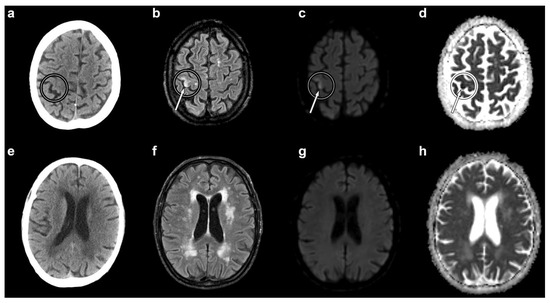

Ischaemic Stroke of the “Hand-Knob” Area Due to Paradoxical Cerebral Air Embolism after Central Venous Catheterization—A Doubly Rare Occurrence: A Case Report and an Overview of Pathophysiology, Diagnosis, and Treatment

by Paola Nicolini, Andrea Arighi, Elisa Gherbesi, Francesco Maria Lo Russo, Clara Mandelli, Giuseppina Schinco, Stefano Carugo and Tiziano Lucchi

Brain Sci. 2022, 12(6), 772; https://doi.org/10.3390/brainsci12060772 - 13 Jun 2022

Central venous catheters (CVCs) are increasingly used across specialties for invasive haemodynamic monitoring and for the delivery of fluids, medications, and nutritional support. Cerebral air embolism (CAE) is a rare but potentially fatal complication associated with the insertion, maintenance, and removal of CVCs. [...] Read more.

Central venous catheters (CVCs) are increasingly used across specialties for invasive haemodynamic monitoring and for the delivery of fluids, medications, and nutritional support. Cerebral air embolism (CAE) is a rare but potentially fatal complication associated with the insertion, maintenance, and removal of CVCs. It can occur through different mechanisms, including the direct retrograde ascension of air into the cerebral veins and paradoxical embolism due to a right-to-left intracardiac or intrapulmonary shunt. The “hand-knob” area is the cortical region within the primary motor cortex that contains the representation of the hand. It is located in the superior precentral gyrus and is the site of less than 1% of all ischaemic strokes. We report here the case of a patient who experienced an ischaemic stroke of the right “hand-knob” area, due to paradoxical CAE through a previously undiagnosed patent foramen ovale (PFO), after the insertion of a catheter in the right internal jugular vein. We also provide an overview of the pathophysiology, diagnosis, and treatment of CAE. Suspecting CAE in the case of an acute neurological event occurring in close temporal relationship with central venous catheterization is paramount to allow the early recognition and treatment of this uncommon form of iatrogenic stroke. Full article

Show Figures

Figure 1